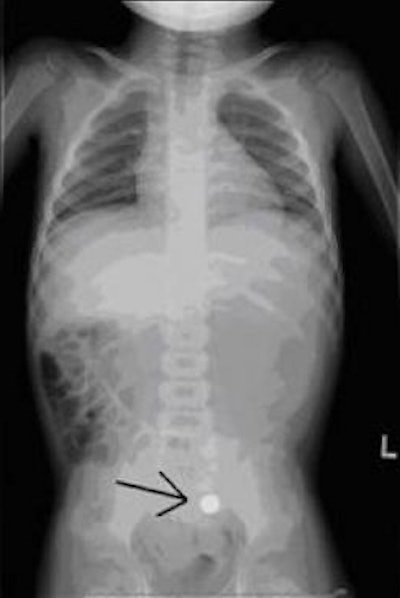

![]() |

| X-ray of a 2-year-old male after swallowing a battery from a Christmas ornament. Image shows the battery (indicated by arrow) has moved into the colon. Image courtesy of Children's Hospital Boston. |

Eighty-six percent of the patients had diagnostic imaging procedures, the majority of which were x-rays (82.8%). Two patients had CT examinations. Thirty-one patients had more than one diagnostic imaging procedure, according to lead author Dr. Amir Kimia, a pediatric emergency medicine specialist.